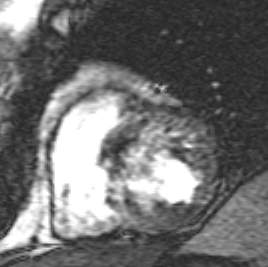

Short axis cine image obtained during suspended respiration

shows dyskinesia of the right ventricular apex.